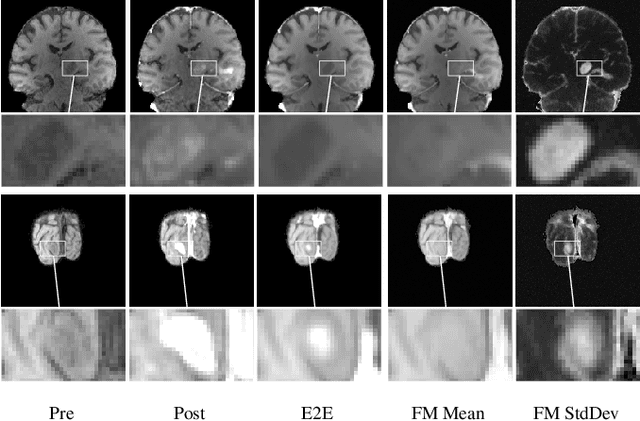

Abstract:Contrast enhancement by Gadolinium-based contrast agents (GBCAs) is a vital tool for tumor diagnosis in neuroradiology. Based on brain MRI scans of glioblastoma before and after Gadolinium administration, we address enhancement prediction by neural networks with two new contributions. Firstly, we study the potential of generative models, more precisely conditional diffusion and flow matching, for uncertainty quantification in virtual enhancement. Secondly, we examine the performance of T1 scans from quantitive MRI versus T1-weighted scans. In contrast to T1-weighted scans, these scans have the advantage of a physically meaningful and thereby comparable voxel range. To compare network prediction performance of these two modalities with incompatible gray-value scales, we propose to evaluate segmentations of contrast-enhanced regions of interest using Dice and Jaccard scores. Across models, we observe better segmentations with T1 scans than with T1-weighted scans.